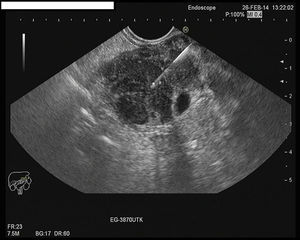

Con la ecoendoscopia o ultrasonografía endoscópica (USE) se puede visualizar un aumento difuso de la glándula, con un parénquima hipoecogénico y puntos hiperecogénicos. El hallazgo de una masa pancreática hipoecogénica puede ser difícil de distinguir del adenocarcinoma. Sin embargo, los puntos hiperecogénicos en la masa hipoecogénica y el signo del ducto penetrante (conducto pancreático no obstruido que atraviesa una masa inflamatoria) son más sugestivos de la PAI que de la neoplasia27. Otro hallazgo típico es el engrosamiento del conducto biliar principal en su porción distal, a expensas sobre todo de la capa muscular más externa28.

Alternativas menos invasivas son la obtención de biopsias por punción percutánea o guiada por USE. Esta última es una opción cada vez más atractiva, ya que permite hacer un examen endosonográfico del páncreas a la vez que se punciona bajo control directo, con una baja tasa de complicaciones29 (fig. 2). Las biopsias trucut permiten la obtención de un cilindro de tejido para el estudio histológico y la detección de células IgG4 por inmunohistoquímica (IHQ), aunque puede tener más complicaciones. La clínica Mayo aboga por este método ya que no se artefacta la organización tisular30. Una alternativa más cómoda y segura es la punción-aspiración con aguja fina (PAAF), con procesamiento de las muestras en bloques celulares y realización de IHQ, aunque su utilidad es más controvertida31-34. Sin embargo, hay que recalcar que la detección de células aisladas no es diagnóstica de PAI y la detección de células IgG4 en tejido no es patognomónica de la PAI tipo 135. Podría plantearse la PAAF como primer paso diagnóstico para descartar una neoplasia pancreática, ya que su precisión diagnóstica para lesiones malignas llega a ser de 94%36,37. En caso de resultado inconcluyente, el siguiente paso sería la realización de trucut biopsia mediante USE.